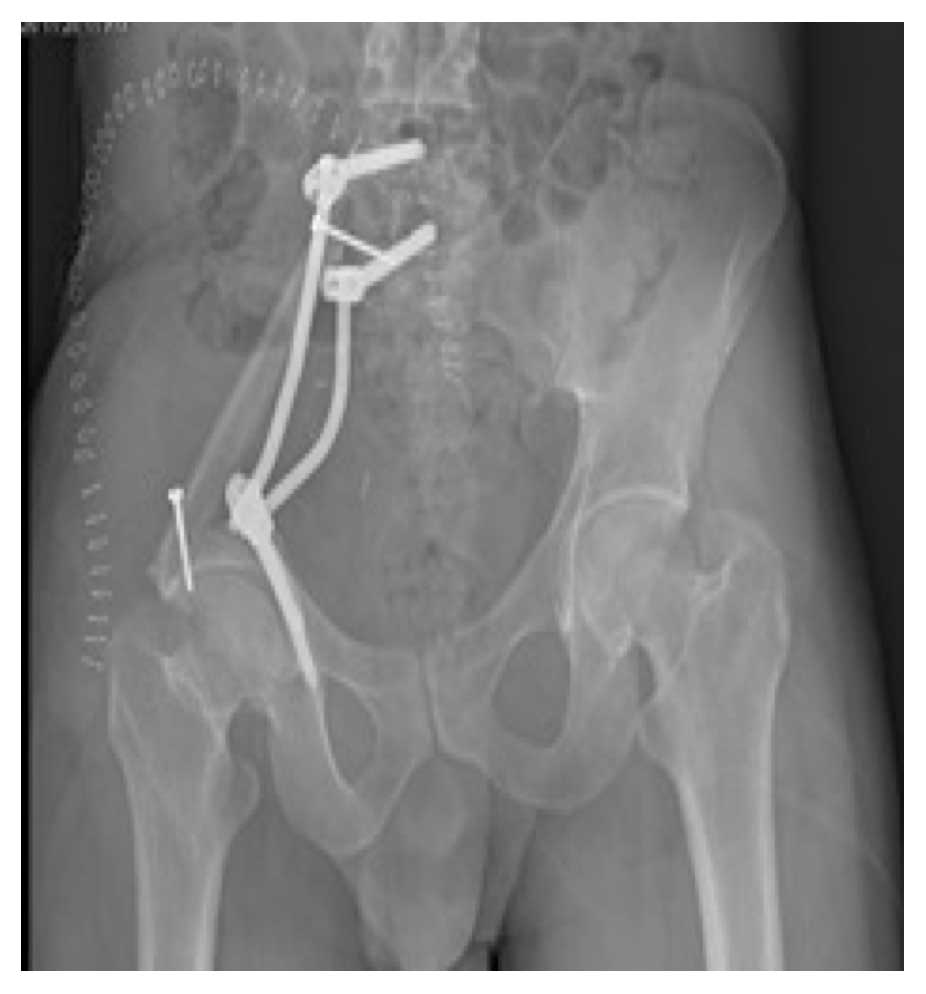

Ameliyat Sonrası: Röntgende sakroiliak rezeksiyon sonrası fibula ve pedikül vidası/rodlar ile rekonstrüksiyon görünmekte.